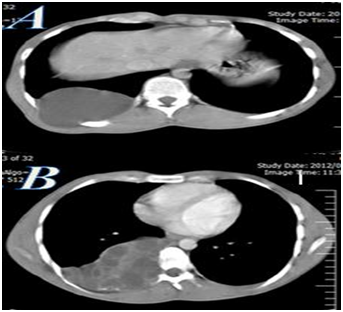

A 19-years-old Iranian male patient was referred to our department in 2011 with history of gradually onset of right chest wall swelling with pain since seven months ago. The patient was living in the rural part of Guilan province in north of Iran. He had not any history of medical or surgical problems. Physical examination showed a localized swelling over the back on the right chest wall without tenderness on palpation (Figure 1). The patient’s laboratory findings were within normal limits. Chest X-rays showed a mass lesion on right hemi thorax with an osteolytic lesion of the 7th rib. Contrast enhanced CT scan revealed a multi loculated mass lesion with septations and enhancement over visceral pleura at the posterior side of thorax that destructed right seventh rib and extended to posterior mediastinum and chest wall (Figure 2). Cystotomy and partial resection of the seventh rib were performed via a right posterolateral thoracotomy. Daughter cysts were seen when the lesion was incidentally opened (Figure 1). Albendazol (800mg daily) was administered for three months postoperatively. Histological findings had confirmed the diagnosis of hydatid cyst. There weren’t any complications during the postoperative period and the patient was discharged at postoperative 5th day in a state of complete recovery. In 1-year follow-up period he was in good condition without recurrence of the chest wall mass.

Figure 2 CT scans of thorax (A,B) with IV contrast showing rib distraction and cystic mass of seven rib.

Hydatid cyst of the rib is important because lead to the destruction of bone matrix and causing the spread of hydatid disease into the surrounding soft tissue and adjacent part of the skeleton.2 In this case, the hydatid cyst was primer lesion; it involved neither the lung nor the liver. A possible mechanism of primary hydatid diseases of chest wall may be the embryo passes through the duodenum wall into either the portal vein or the perideuodenum and perigastric lymphatics, which connect to the thoraco-mediastinal lymphatics and the thoracic duct.4 The course of the disease is usually slow and serology may not always be helpful in diagnosing primary skeletal hydatidosis. These patients are usually asymptomatic but some time present with chest wall pain2 as our patient complaint was chest wall pain and swelling. In the presented patient, imaging modalities such as contrast enhanced CT scan revealed a multi loculated mass lesion with septations and enhancement over visceral pleura at the posterior side of thorax and the differential diagnosis of such a radiographic picture includes giant cell tumor, osteolytic metastases, plasmacytoma, aneurysmal bone cyst and cystic neuro fibromas.5